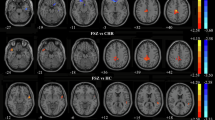

In the rs-fMRI images, PRS subjects showed significant ReHo decreases in the left inferior temporal gyrus (t = −4.256, corrected p < 0.005), but increases in the right inferior frontal gyrus (t = 4.011, corrected p < 0.005) and right putamen (t = 4.333, corrected p < 0.005) compared with the controls. The details are shown in Table 2 and Fig. 1.

The key finding of this study is that PRS subjects exhibited a significantly lower ReHo in the left inferior temporal gyrus and significantly higher ReHo in the right inferior frontal gyrus and right putamen relative to the controls during the resting state. No correlations between the abnormal regional functional synchronization in these brain regions and the clinical characteristics existed. Further ROC analysis showed that the ReHo values in these brain regions, including the left inferior temporal gyrus, right inferior frontal gyrus and right putamen, might not be used as potential markers to identify the PRS subjects from the controls, individually. However, the SVM analysis revealed that a combination of ReHo values in the three brain regions could serve as a right marker with a sensitivity of 88.24%, a specificity of 91.89% and an accuracy of 90.14% for discriminating the PRS subjects from the controls.